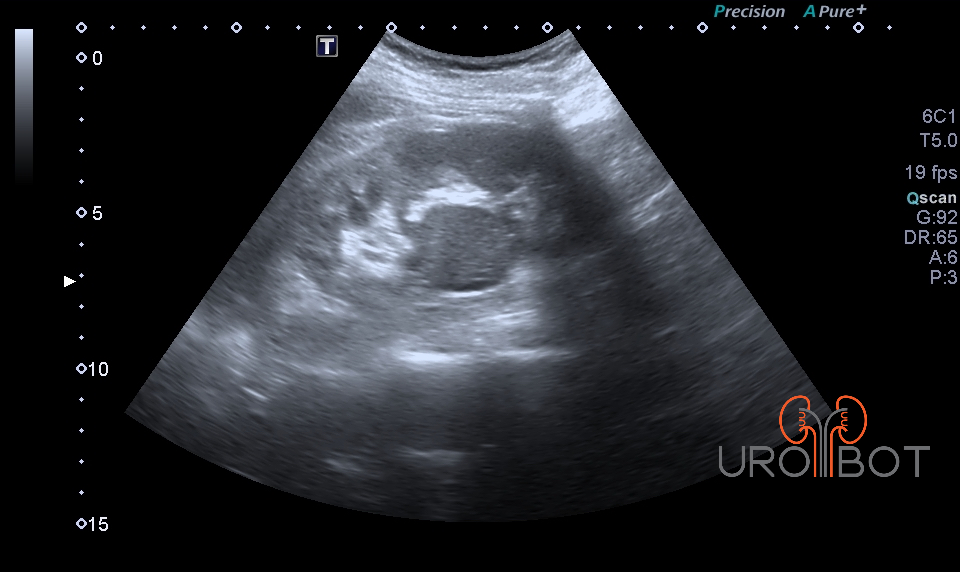

Niere mit Tumor

Auf diesem Bild erkennt man in der sog. Hilusregion einen rundlichen Tumor